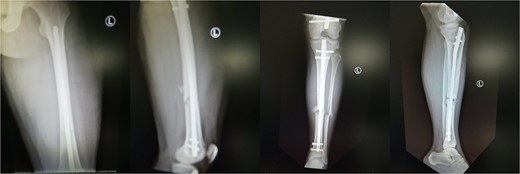

A 19-year-old male patient was admitted to the orthopedic department of our institution after a motorbike accident. The patient sustained a diaphyseal fracture of the left femur and ipsilateral tibia (floating knee) (Fig. 1), along with a right acromioclavicular joint type II injury and a right minimally displaced distal radius fracture. The patient was scheduled for emergent surgery. He underwent a retrograde intramedullary nailing of the left femur and an antegrade intramedullary nailing of the left tibia, under general anesthesia (Fig. 2). The operation was performed with the patient in the lithotomy position. The right intact leg was applied in 1000 of the hip flexion and 900 of the knee flexion. The duration of the surgery was 4 h and 20 min.

Ipsilateral femoral and tibial shaft fracture of the left limb (floating knee).

Post-operative view of the left femur and tibia. Concomitant retrograde IM nailing and antegrade IM nailing were performed.